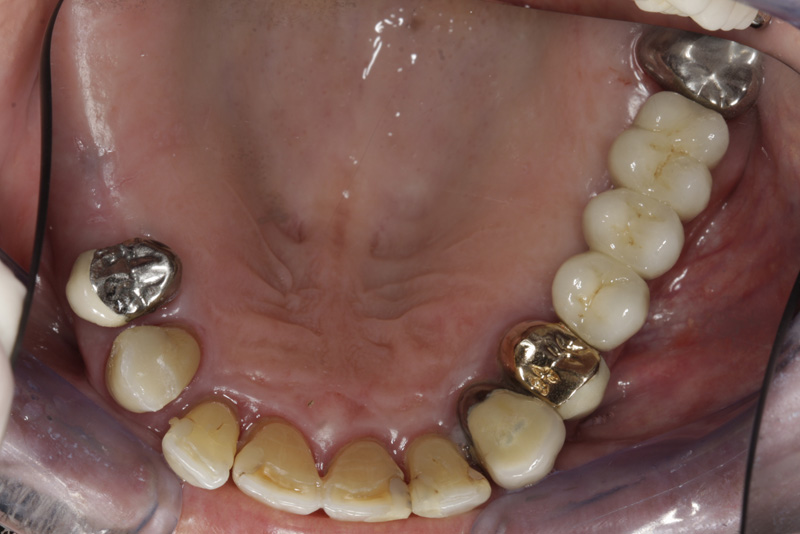

Během let může postupnou ztrátou zubů zůstat v ústech omezený počet zubů, které umožňují držení zubních náhrad.

V důsledku přetížení zbylých zubů např. houpavými pohyb snímacích náhrad dochází k uvolnění těchto zubů a držení můstků a protéz je tak velmi těžké. V těchto případech můžeme pomocí implantátů zvýšit počet pilířů a tím zabránit přetěžování a ztrátě zbylých zubů

V případě chybění většího počtu zubů v postranních úsecích čelistí je možné ošetření pomocí implantátů, které nahradí ošetření pomocí snímacích náhrad kotvených na zbývajících zubech nebo patře.

Podmínkou je opět dostatečné množství kosti.